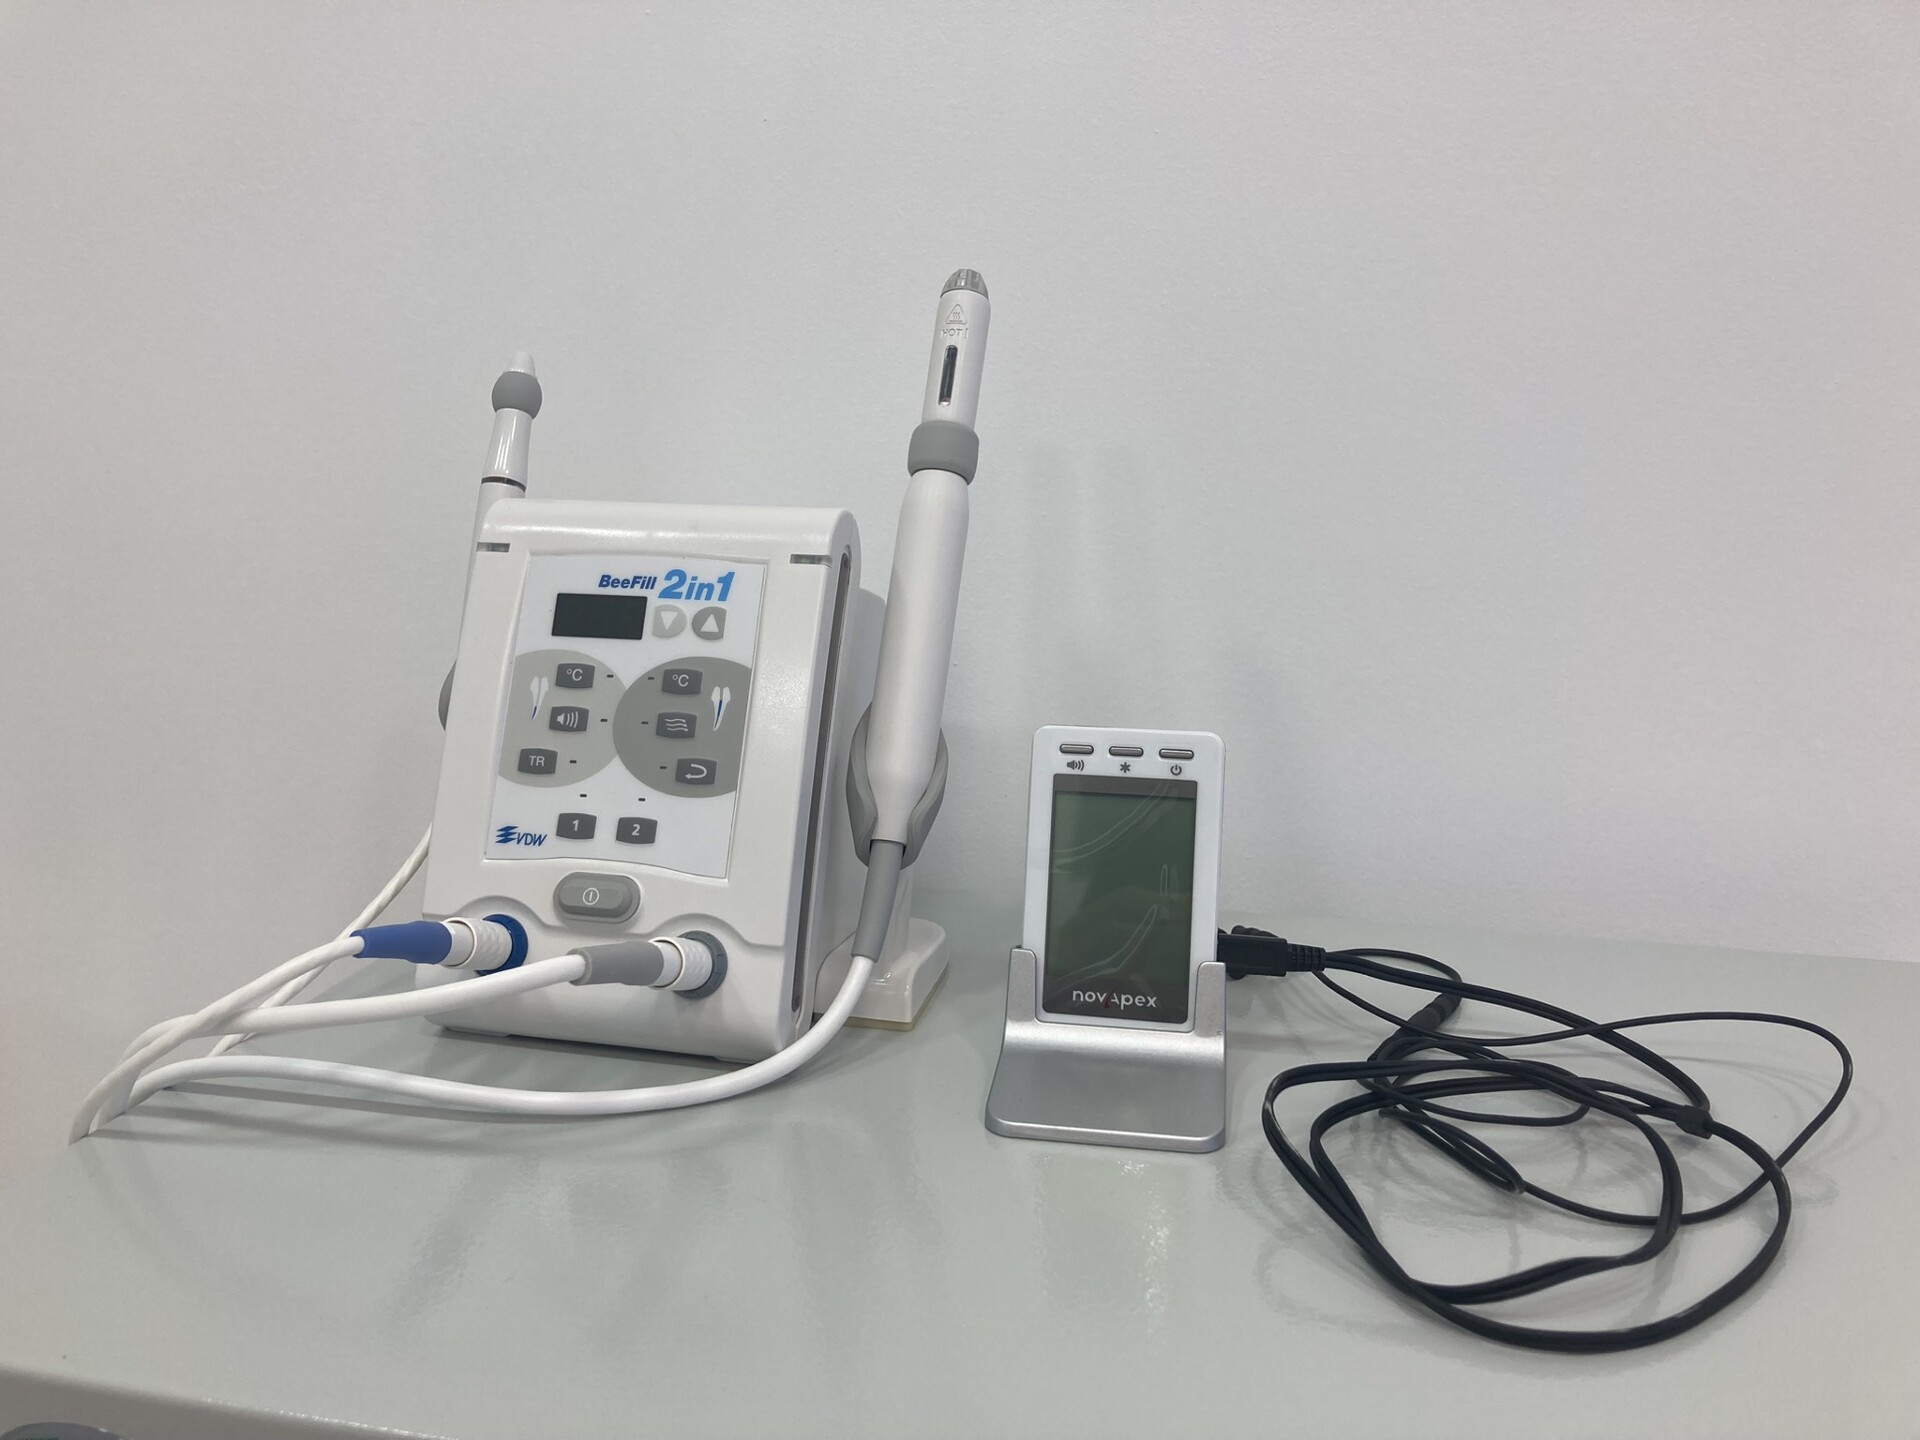

Добро пожаловать на сайт нашей цифровой стоматологической клиники! Мы рады предложить вам широкий спектр услуг по уходу за полостью рта. Наша клиника оснащена самым современным оборудованием, что позволяет нам предоставлять высококачественные услуги в комфортной и безопасной обстановке.

В нашем стоматологическом центре оказываются услуги комплексной диагностики зубов с применением инновационных методик, новейших технологий и современного оборудования

Составим индивидуальный план лечения с использованием новейших цифровых технологий